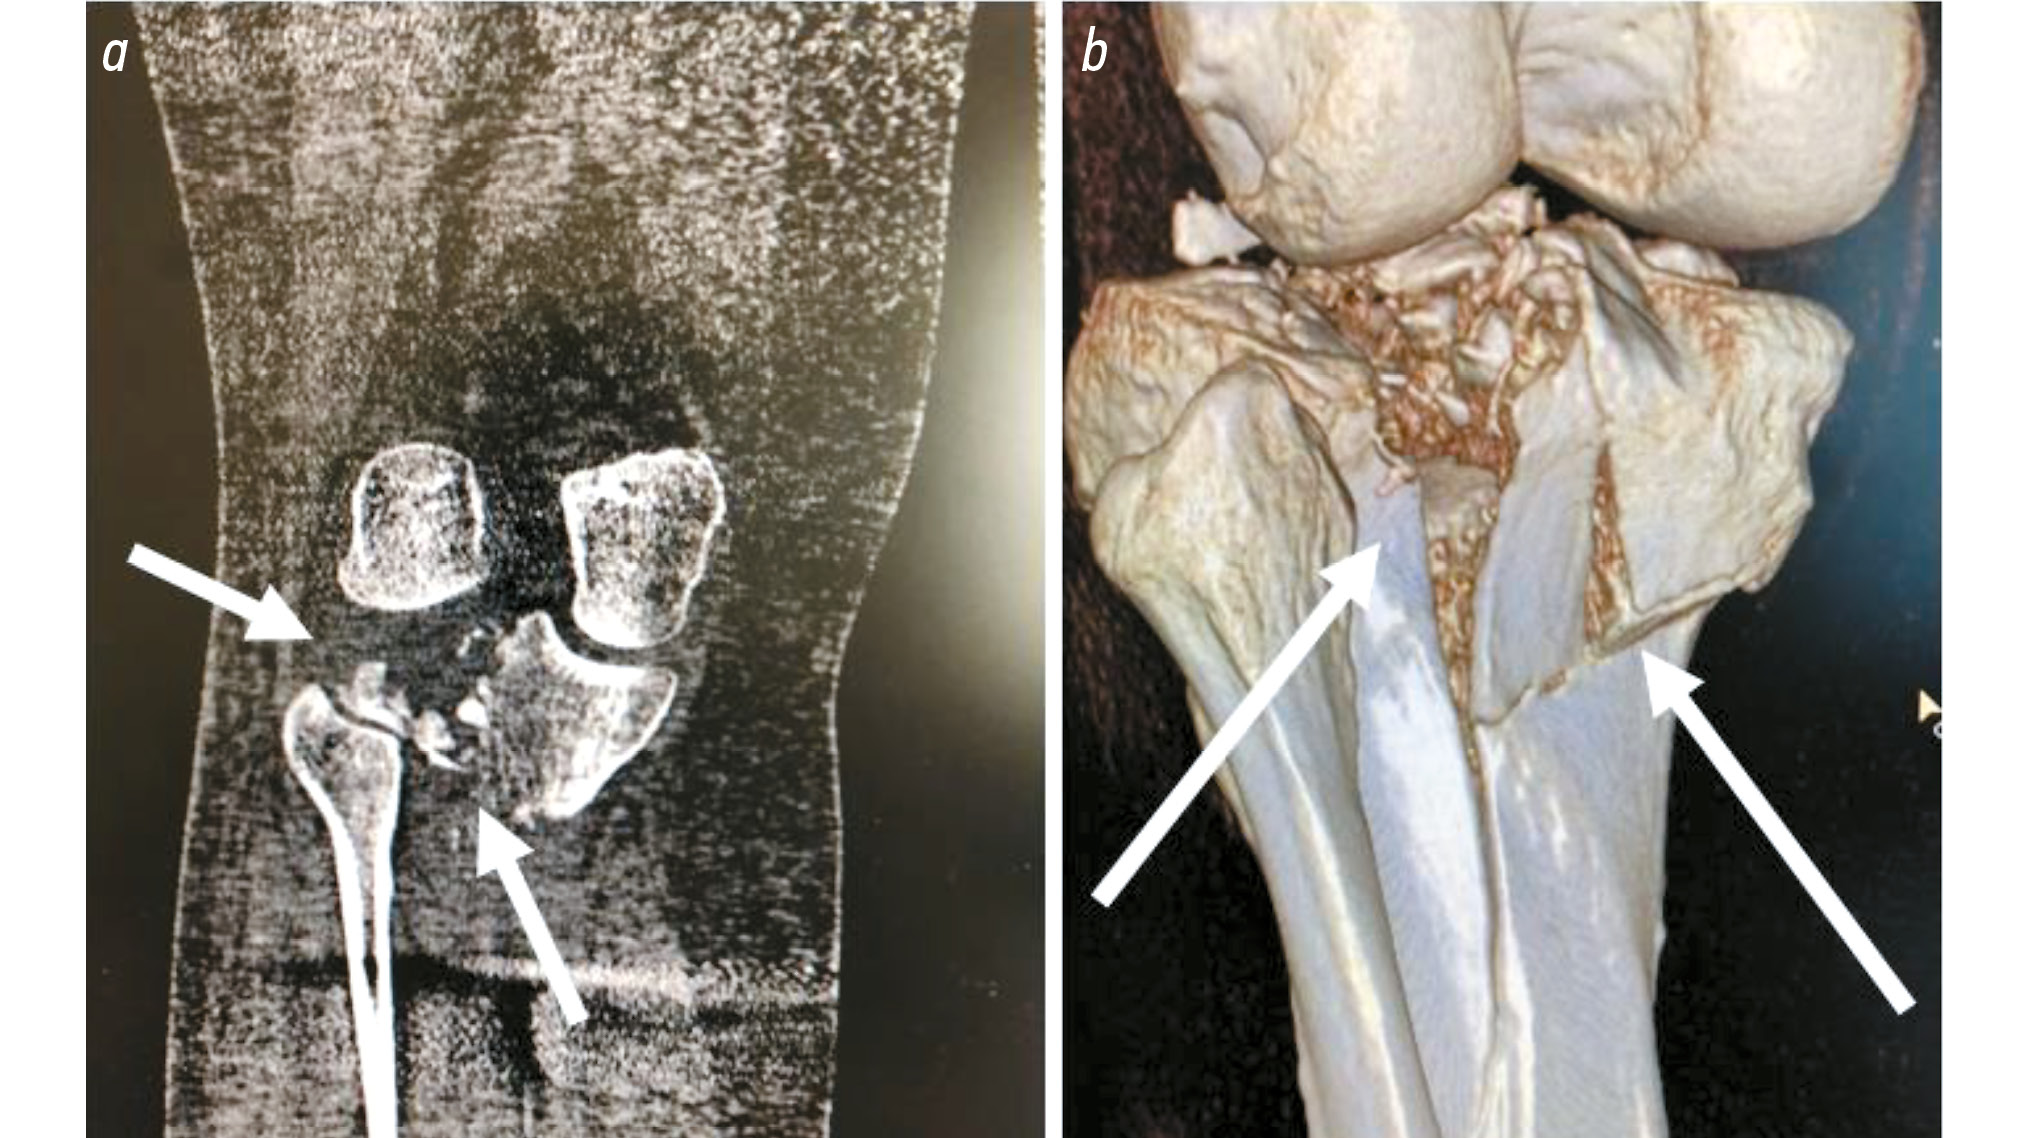

Переломы костей голени при падении имели место в 33 случаях, при этом большеберцовая кость страдала наиболее часто (n=28). При падении у самокатчиков наблюдались переломы всех сегментов костей голени, однако переломы так называемого плато большеберцовой кости (рис. 3) наблюдались в половине случаев её переломов (n=14). Такие переломы были закрытыми, оскольчатыми (или многооскольчатыми), вдавленными, локализовались на одном (наружном, внутреннем) либо обоих мыщелках кости, а наружные повреждения в их проекции отсутствовали.

Рис. 3. Компьютерная томография коленного сустава, выполненная пострадавшему после падения с электросамоката: а ― стрелками обозначена локализация многооскольчатого перелома мыщелка большеберцовой кости; b (3d-реконструкция) ― стрелками обозначена локализация оскольчатого перелома на уровне плато (мыщелка) большеберцовой кости.